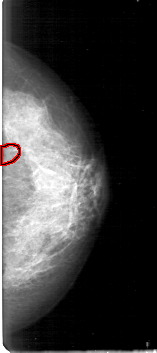

D_4158_1.LEFT_MLO

LEFT_MLO LINES 5371 PIXELS_PER_LINE 2641 BITS_PER_PIXEL 12 RESOLUTION 43.5 OVERLAY

FILE: D_4158_1.LEFT_MLO.OVERLAY

TOTAL_ABNORMALITIES 1

ABNORMALITY 1

LESION_TYPE CALCIFICATION TYPE PLEOMORPHIC DISTRIBUTION CLUSTERED

ASSESSMENT 0

SUBTLETY 3

PATHOLOGY MALIGNANT

TOTAL_OUTLINES 1

BOUNDARY